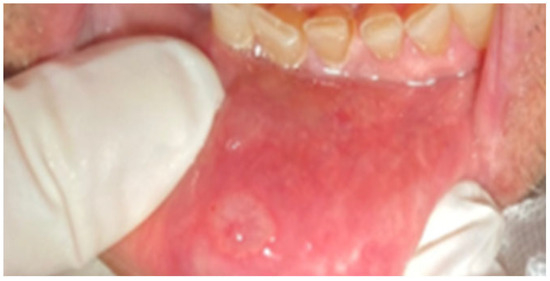

3.1. Recurrent Aphthous Stomatitis

3.2. Aphthous Ulcers